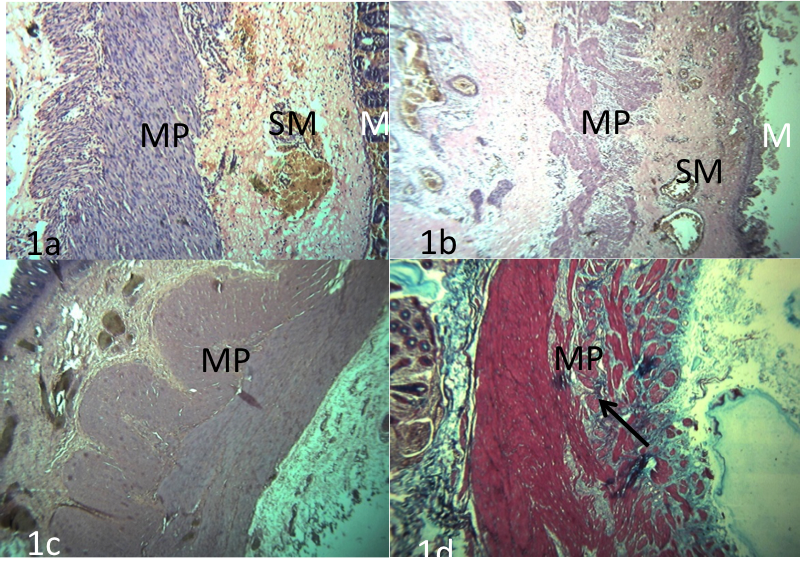

• Study of pouch colon affected pro-bands in Rajasthan